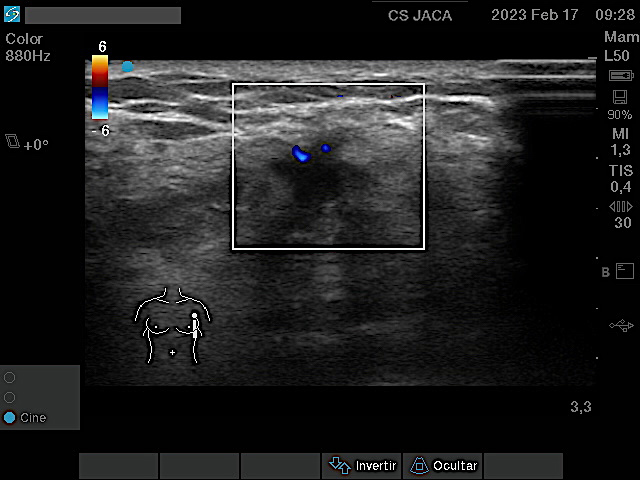

Mostramos las imágenes ecográficas de cada una de esas 5 neoplasias obtenidas desde la Atención Primaria, en modo 2D y tras estudio Doppler. Los tumores variaban de 8 a 30 mm en su eje mas largo. Salvo uno, el resto mostraba características típicas: bordes irregulares, espiculados, estructura hipoecogénica, actividad Doppler interna y ausencia de refuerzo posterior.